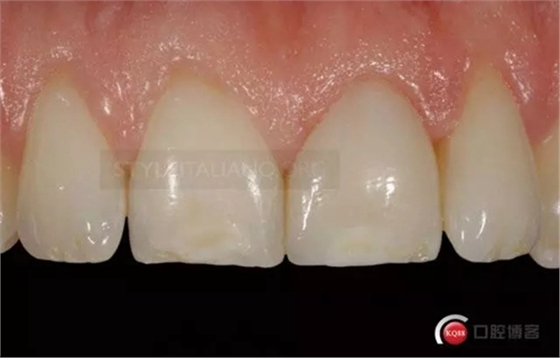

Control one month check shows a natural smile

And the vestibular

and palatal tissue healing